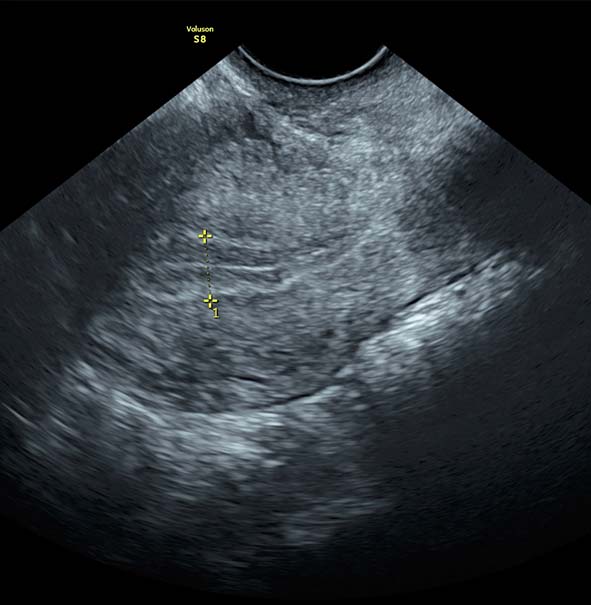

Se realiza ultrasonido vaginal para valorar crecimiento folicular. (usualmente son de 2 a 3 citas)